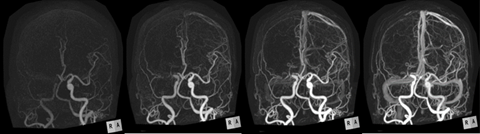

また16センチメートルの範囲を繰り返し撮影することで、形態情報画像に時間軸の動態情報をプラスした4D-CTイメージが得られます。頭部領域での4D-CTでは、脳血管全体を動脈相から静脈相まで観察することが可能で、急性期脳梗塞の診断や短絡疾患に対する流入動脈および流出静脈の同定に有用です。

4D-CTイメージ